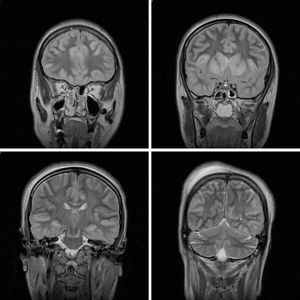

This case is a 26-year-old female in whom MRI imaging was done24 hours after an attempted hanging episode.